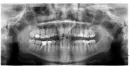

Ставлю коронку на 5-й и 6-й зубы.

Вчера сделали слепки, врач поставил временную коронку одну на два зуба. То есть их как бы две, но связанные между собой.